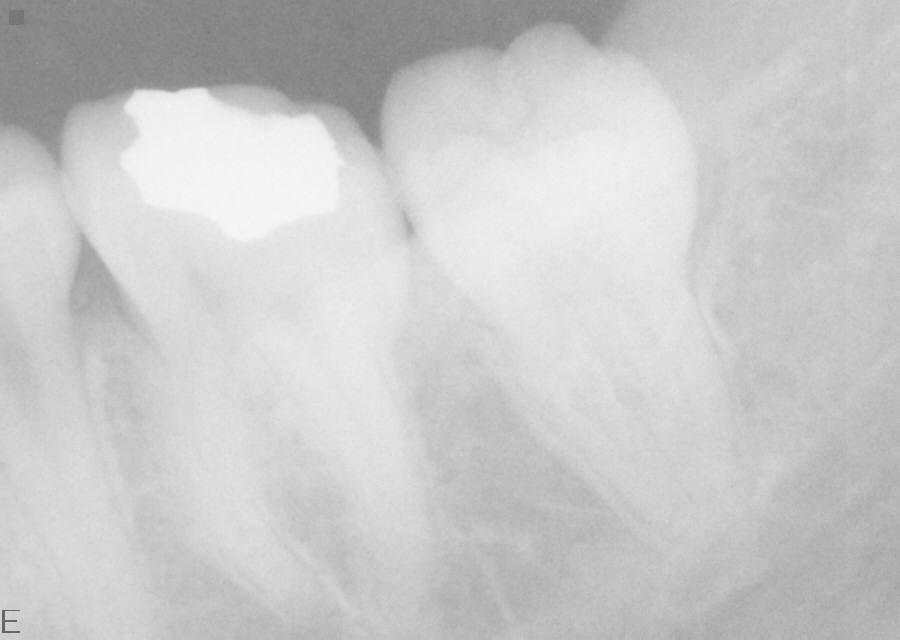

フィルムの代わりに、このようなCCDセンサーで撮影します。3秒ほどでモニターに映し出されます

アメリカのSchick社製のデジタルレントゲン"CDRシステム"を導入しております。